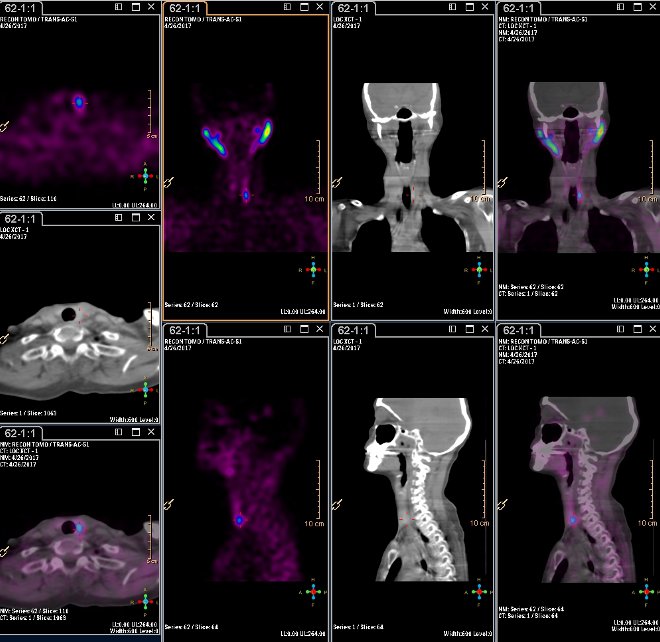

/ Obr. 3.: Scintigrafie pomocí 99mTc-MIBI metodou SPECT/ldCT s patologickou ložiskovou depozicí radiofarmaka při dorzálním okraji dolního pólu levého laloku štítnice.

Nález: Na planárních snímcích obraz zvýšené akumulace Tc-MIBI s projekcí k dolnímu pólu levého laloku štítnice se zřetelně zpomaleným vymýváním RF, který se zvýrazňuje po provedení počítačové subtrakce.

Při SPECT pak patologická akumulace lokalizována k dorzálnímu okraji dolního pólu levého laloku štítné žlázy.

Res.: susp. patologie příštitného tělíska vlevo dole.

Diskuse: Z výše uvedeného vyplývá přínos hybridního vyšetření SPECT/ldCT kombinované scintigrafie příštítných tělísek při detekci a lokalizaci patologicky změněného příštítného tělíska při nejednoznačném nálezu scintigrafickém.